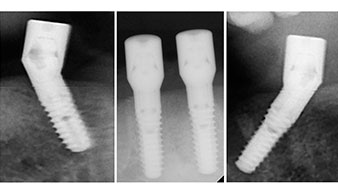

Zur Planung und Risikominimierung wurde eine dreidimensionale Volumentomografie (DVT, Planmeca) erstellt. Dieses zeigte, dass die Qualität und Quantität des Knochens für eine Operation und Sofortversorgung nach der Fast & Fixed-Methode ausreichend war. Nach Protokoll dieses Konzeptes wird in Regio 35, 32, 42 und 45 implantiert. Durch die bis zu 45-Grad-Schiefstellung der distalen Implantate wird das Durchtrittsprofil nach posterior verlegt und ein größeres Stützpolygon erreicht (Abb. 3).

Fast & Fixed-Methode

Abb. 3